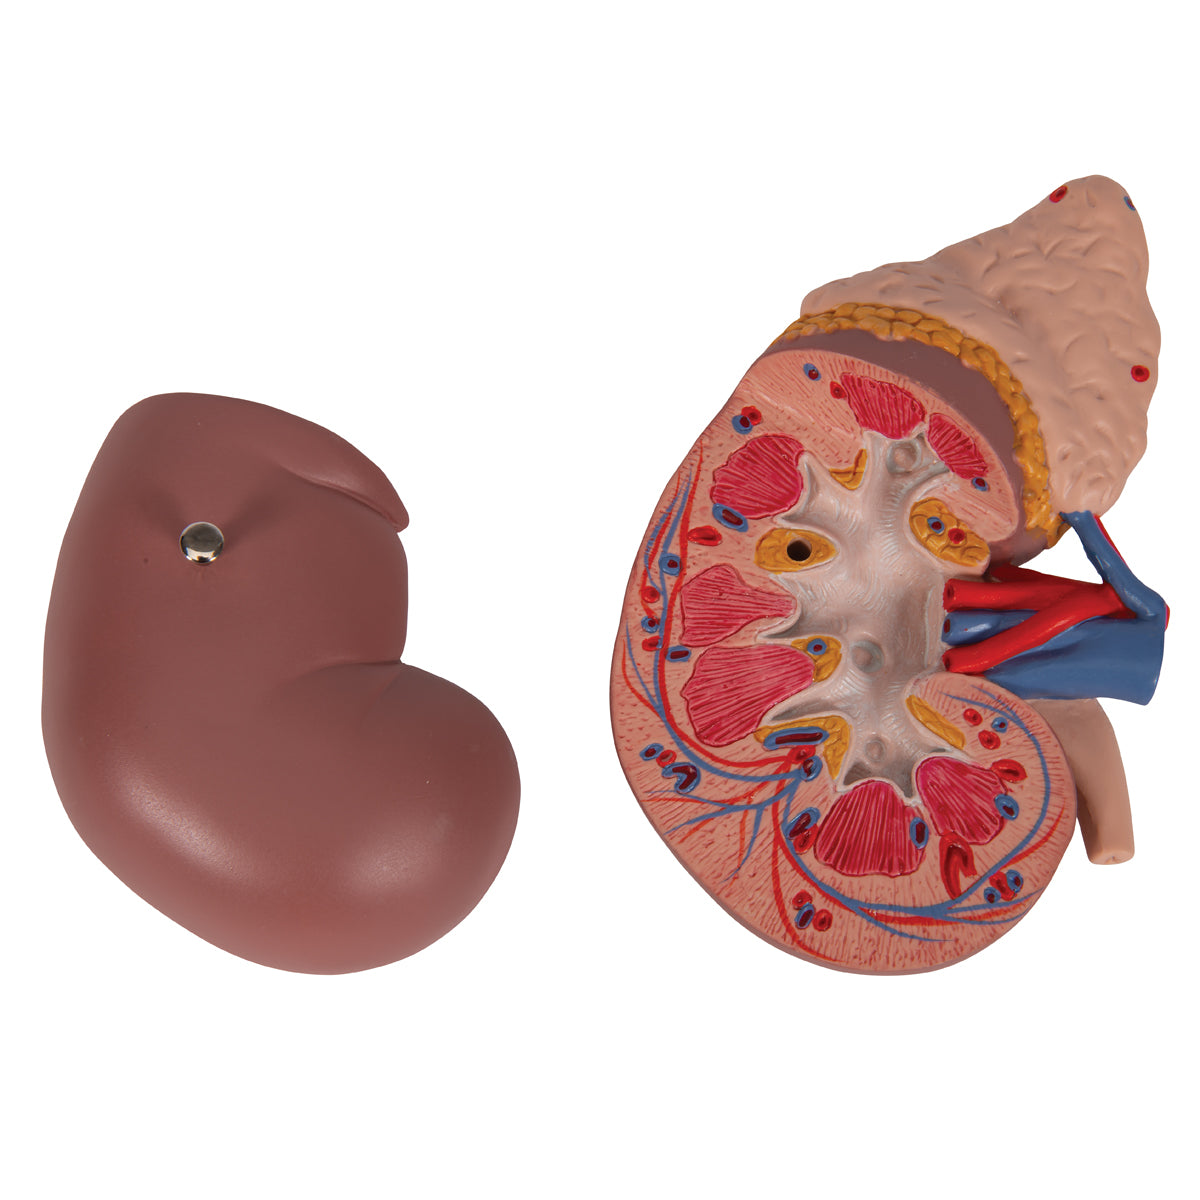

El riñón con glándula adrenal, en 2 piezas

El riñón con glándula adrenal, en 2 piezas

Este modelo presenta:

• El riñón con glándula adrenal

• Conductos renales y adrenales

• Parte superior del uréter

La parte delantera del riñón es desmontable para poder demostrar la corteza de la médula y los conductos así como la pelvis renal. Sobre base desmontable.